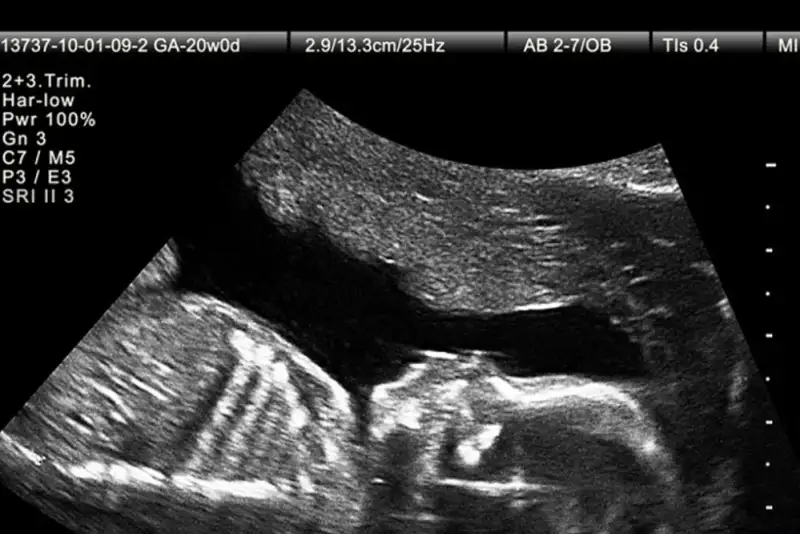

نورنیوز - گروه  اجتماعی: در سال‌های اخیر پیشرفت‌های تصویربرداری در بارداری به پزشکان امکان داده تا زودتر از گذشته ناهنجاری‌های جنینی را تشخیص دهند. یکی از شاخص‌هایی که در این مسیر اهمیت زیادی یافته، وضعیت استخوان بینی جنین است که می‌تواند نشانه‌ای از برخی اختلالات ژنتیکی باشد.

اختلالات کروموزومی مانند سندرم داون از شایع‌ترین ناهنجاری‌های ژنتیکی در میان نوزادان هستند. این وضعیت در حدود یک مورد از هر ۸۰۰ تولد زنده دیده می‌شود و به دلیل تأثیر آن بر رشد ذهنی و جسمی کودک، شناسایی زودهنگام اهمیت زیادی دارد. از سال‌ها پیش، پزشکان متوجه شدند که نبود یا کوچکی استخوان بینی جنین می‌تواند یکی از نشانه‌های احتمالی سندرم داون باشد. با این حال، این یافته در جمعیت‌های مختلف، از نظر نژادی و جغرافیایی تفاوت‌هایی دارد و همین مسئله ضرورت انجام مطالعات اختصاصی برای هر منطقه را نشان می‌دهد.

در راستای مطالعه بیشتر این موضوع، میترا افتخار یزدی، دانشیار گروه زنان و مامایی دانشکده پزشکی دانشگاه علوم پزشکی سبزوار، به همراه پنج همکار خود، پژوهشی را برای بررسی ارتباط اندازه استخوان بینی جنین با بروز سندرم داون انجام داده‌اند. این مطالعه با هدف یافتن رابطه میان مشاهده یا عدم مشاهده استخوان بینی در دو مرحله از بارداری یعنی سه‌ماهه اول و دوم طراحی شده است تا مشخص شود آیا این شاخص می‌تواند به‌تنهایی معیار مناسبی برای تشخیص زودهنگام ناهنجاری‌های ژنتیکی باشد یا خیر.

در این پژوهش، ۲۶۵ خانم باردار مراجعه‌کننده به کلینیک پریناتولوژی دانشگاه علوم پزشکی سبزوار مورد بررسی قرار گرفتند. در این مطالعه، جنین‌هایی که در سونوگرافی سه‌ماهه اول استخوان بینی آن‌ها مشاهده نمی‌شد یا در سه‌ماهه دوم دچار کوتاهی غیرطبیعی این استخوان بودند، وارد تحقیق شدند. داده‌های استخراج‌شده از پرونده بیماران با استفاده از نرم‌افزار آماری مخصوص تحلیل شد تا ارتباط میان اندازه استخوان بینی و نتایج ژنتیکی مشخص شود.

نتایج نشان دادند که در سونوگرافی سه‌ماهه اول، حدود ۳۱ درصد از جنین‌ها فاقد استخوان بینی بودند. از میان این موارد، ۱۹ درصد مبتلا به سندرم داون و سایر اختلالات ژنتیکی بودند، در حالی‌که در سه‌ماهه دوم، هرچند درصد بیشتری از جنین‌ها دچار کوتاهی استخوان بینی بودند، اما این ویژگی به‌تنهایی ارتباط آماری خاصی با ناهنجاری‌های ژنتیکی نشان نداد. به بیان ساده‌تر، اگر در ماه‌های اول بارداری استخوان بینی دیده نشود، احتمال وجود اختلال ژنتیکی بالا است، ولی در ماه‌های بعد، کوتاهی آن الزاماً به معنای وجود چنین اختلالی نیست.

محققان نتیجه گرفتند که نبود استخوان بینی در سونوگرافی سه‌ماهه اول می‌تواند به‌عنوان یک شاخص مهم در غربالگری‌های پیش از تولد مورد توجه قرار گیرد، اما در سه‌ماهه دوم نمی‌توان تنها بر پایه اندازه کوچک استخوان بینی تصمیم‌گیری کرد. به عبارت دیگر، در نیمه دوم بارداری لازم است عوامل دیگری مانند سایر شاخص‌های سونوگرافی یا سوابق خانوادگی نیز بررسی شود تا تشخیص دقیق‌تر صورت گیرد.